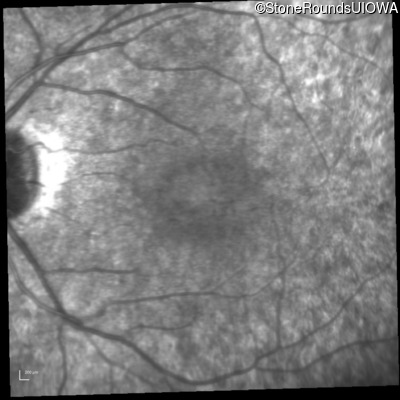

Infrared Fundus Photograph - Right - 20/25 -2

Exemplar

Infrared Fundus Photograph - Left - 20/32